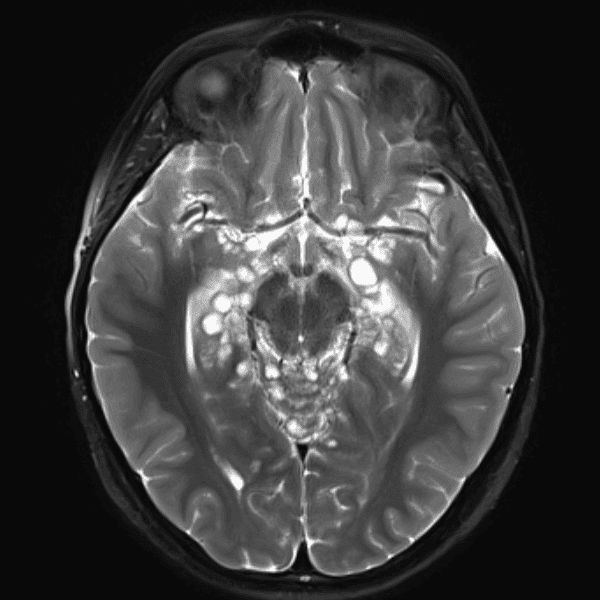

Classic Cases